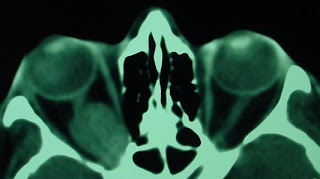

Neuropatía óptica compresiva

La neuropatía óptica compresiva puede ser producida por tumores (gliomas, meningioma, hemangiomas, otros), por aneurismas o por un aumento del volumen de los músculos extraoculares (orbitopatía tiroidea).

Sus manifestaciones clínicas generalmente aparecen de forma gradual, no abruptamente, y consisten en disminución de la agudeza visual, alteración del reflejo fotomotor (con defecto pupilar aferente relativo), alteraciones del campo visual (generalmente escotomas centrales). Puede acompañarse de exoftalmo en grado variable. En el fondo de ojo la papila óptica se puede presentar normal o con diversos grados de palidez, lo que depende del tiempo de evolución de la lesión que comprime el nervio. A veces hay edema de papila, pero es más raro.

El tratamiento consiste en el tratamiento de la causa. Es fundamental sospechar esta enfermedad en pacientes con disminución lenta de la agudeza visual, para lo que la clave es el examen de las pupilas y campos visuales. Los estudios de neuroimágenes, como la tomografía axial computarizada y la resonancia magnética, confirman el diagnóstico.